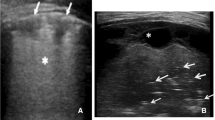

The World Health Organization (WHO) case management algorithm for acute lower respiratory infections has moderate sensitivity and poor specificity for the diagnosis of pneumonia. We sought to determine the feasibility of using point-of-care ultrasound in resource-limited settings to identify pneumonia by general health practitioners and to determine agreement between the WHO algorithm and lung consolidations identified by point-of-care ultrasound.

An expert radiologist taught two general practitioners how to perform point-of-care ultrasound over a seven-day period. We then conducted a prospective study of children aged 2 months to 3 years in Peru and Nepal with and without respiratory symptoms, which were evaluated by point-of-care ultrasound to identify lung consolidation.

We enrolled 378 children: 127 were controls without respiratory symptoms, 82 had respiratory symptoms without clinical pneumonia, and 169 had clinical pneumonia by WHO criteria. Point-of-care ultrasound was performed in the community (n = 180), in outpatient offices (n = 95), in hospital wards (n = 19), and in Emergency Departments (n = 84). Average time to perform point-of-care ultrasound was 6.4 ± 2.2 min. Inter-observer agreement for point-of-care ultrasound interpretation between general practitioners was high (κ = 0.79, 95 % CI 0.73–0.81). The diagnosis of pneumonia using the WHO algorithm yielded a sensitivity of 69.6 % (95 % CI 55.7–80.8 %), specificity of 59.6 % (95 % CI 54.0–65.0 %), and positive and negative likelihood ratios of 1.73 (95 % CI 1.39–2.15) and 0.51 (95 % CI 0.30–0.76) when lung consolidation on point-of-care ultrasound was used as the reference.

The WHO algorithm disagreed with point-of-care ultrasound findings in more than one-third of children and had an overall low performance when compared with point-of-care ultrasound to identify lung consolidation. A paired approach with point-of-care ultrasound may improve case management in resource-limited settings.